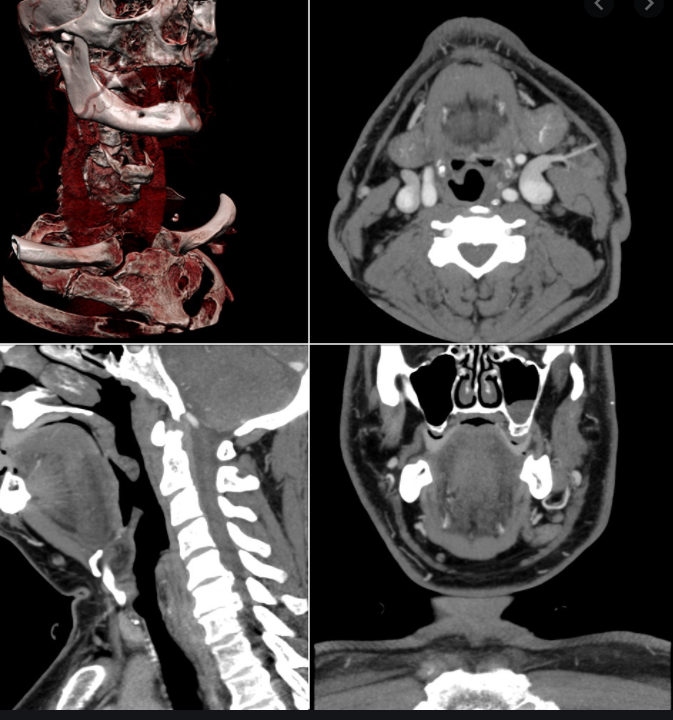

전리방사선 및 비전리방사선의 취급과 방사성동위원소를 이용한 행의학검사와 초음파검사 등 관리 및 취급 업무를 하는 사람을 말합니다. 보통 병원에 가서 엑스레이 검사를 하거나, CT, MRI 검사를 하는 사람들이 방사선사이고, 핵의학과, 방사선종양학과에서 일하는 사람도 방사선사입니다.